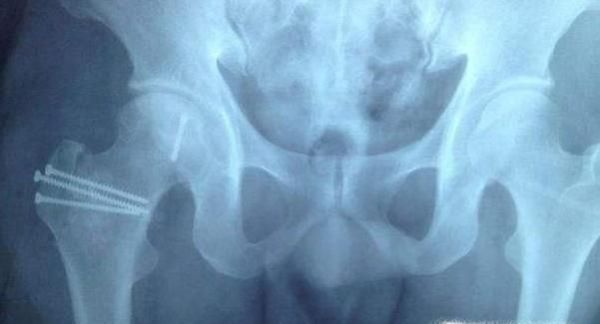

03、常见疾病肱骨头最常见的疾病就是肱骨头坏死,又称无菌性股骨头坏死。发病原因是肱骨头供血不足,进而导致肱骨头骨质坏死。

08、有因才有果。据不完全统计有将近四十多种因素都能导致股骨头坏死。大致股骨头坏死可分为创伤性和非创伤性两大类,前者主要是由股骨颈骨折、髋关节脱位等髋部外伤引起,后者在我国的主要原因为酗酒、激素、先天因素等造成。除此之外,风、寒、湿的环境、减压病(长期从事潜水、飞行工作)等因素也会影响股骨头的血运,易发股骨头缺血性坏死。自己对号入座吧。